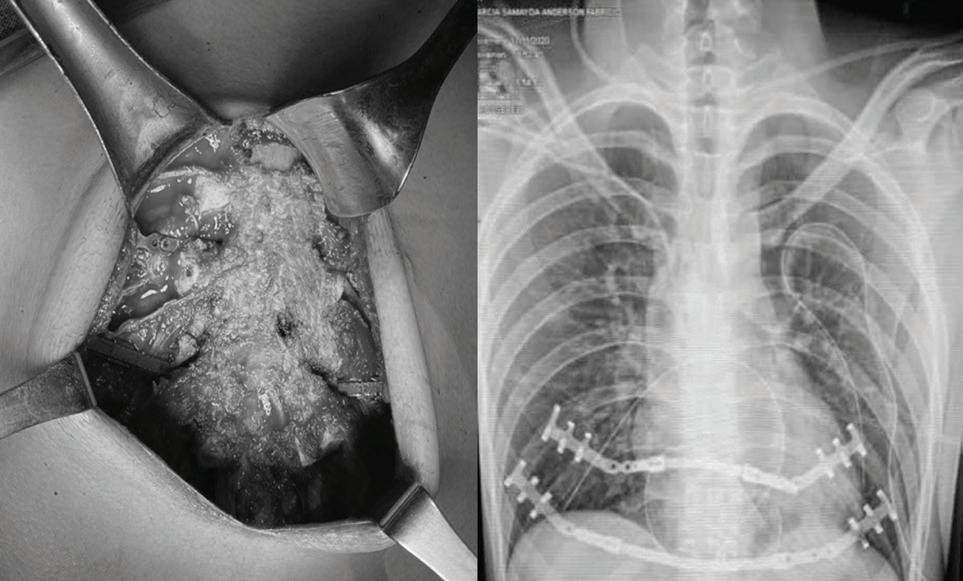

El paciente fue operado en decúbito supino bajo anestesia general. Se realizó una incisión en la línea media sobre el cuerpo esternal, y se disecan flaps miocutaneos para exponer los cartilagos costales deformados, resecando 05 cartilagos de cada lado, preservando su pericondrio posterior (Foto 3).

Durante la resección de los cartílagos costales hubo una ruptura pleural del lado izquierdo. El cuerpo esternal estaba profundamente deformado, por lo que se realizó una osteotomia cuneiforme en el punto de angulación posterior del esternón para permitir que el esternón se incline hacia adelante en la posición adecuada. Finalmente, el cuerpo esternal se estabilizó con dos barras de titanio retroesternales y se acopló a clips de titanio en los arcos costales (Foto 4). Se colocó un drenaje cerrado al vacío sobre el músculo y se colocó un tubo de toracotomía izquierdo.

Paciente en su postoperatorio es trasladado a unidad de cuidados intensivos de adultos, donde permanece estable bajo monitoreo constante y analgesia por catéter epidural, en donde permanece por 3 días y posteriormente es trasladado al servicio de cirugía de hombres donde se omite sonda de toracostomía y se da egreso al octavo día postoperatorio. Paciente con seguimiento en consulta externa con adecuada evolución (Foto 5).